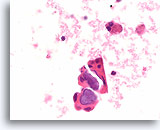

Afbeelding 23

Cellulair laesie, folliculair neoplasma kan niet worden uitgesloten (hürthlecelneoplasma vs lymfocytische thyroïditis), schildklier, ThinPrep®.

Er is een microfolliculaire groep hürthlecellen met enkele mogelijke lymfocyten aanwezig.

60X

Afbeelding 23

Cellulair laesie, folliculair neoplasma kan niet worden uitgesloten (hürthlecelneoplasma vs lymfocytische thyroïditis), schildklier, ThinPrep®.

Er is een microfolliculaire groep hürthlecellen met enkele mogelijke lymfocyten aanwezig.

60X